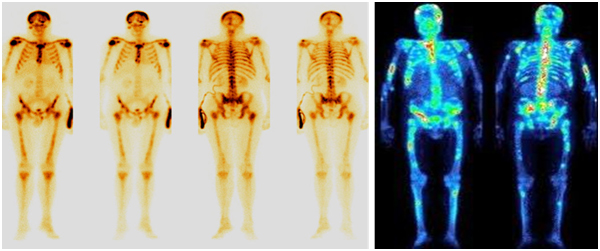

Остеосцинтиграфия

Остеосцинтиграфия – это метод радионуклидной лучевой диагностики, который оценивает специфическое поражение костей, развивающееся на фоне злокачественного процесса.

Таким образом, лучевые методы исследования необходимы как до начала лечения в целях диагностики и оценки распространённости опухолевого процесса, так и в процессе лечения, чтобы отслеживать изменения опухолевой массы.